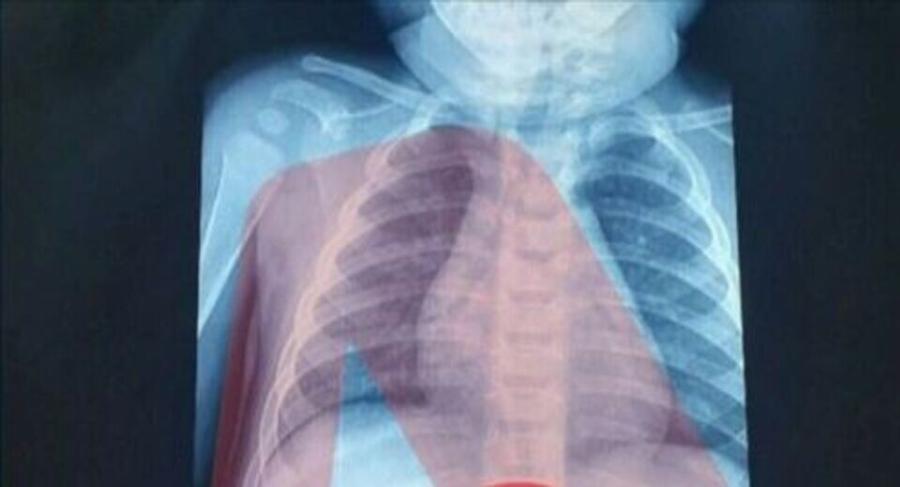

Με ένα απίστευτο περιστατικό ήρθαν αντιμέτωποι οι γιατροί σε νοσοκομείο Παίδων στην Αθήνα, όπου έφτασε 3χρονο αγοράκι που είχε καταπιεί ξυραφάκι.

Ένας 3χρονος μεταφέρθηκε εσπευσμένα στο νοσοκομείο, το οποίο κατάπιε ένα ξυραφάκι. Το παιδί αφού έφτασε σε Παίδων της Αθήνας, υποβλήθηκε άμεσα σε ακτινογραφία, η οποία έδειξε ότι όντως υπήρχε το αιχμηρό αντικείμενο στο στομάχι του

Όπως ενημέρωσαν οι γιατροί, τους γονείς του παιδιού, μετά την ακτινογραφία προσδιορίστηκε και το ακριβές σημείο όπου βρέθηκε το ξυραφάκι, ώστε οι χειρουργοί να προχωρήσουν σε επέμβαση αφαίρεσής του με ασφάλεια.